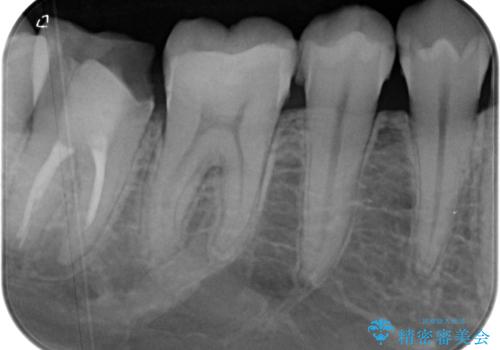

- 右下の奥歯が大きく欠けてしまったのを治したいと来院された患者様です。

舌側の歯冠がなくなってしまっていて、健全な歯質が歯茎の下にある状態です。

このままの状態だと土台がたてられず被せものがいれられないため、歯肉の切除と歯槽骨の形態修正を行い、歯の健全な部分が歯肉の外に出てくるようにしたうえで、オールセラミッククラウンによる補綴治療を行うこととしました。

根管治療のやり替えも提案しましたが、希望されなかったため行いませんでした。